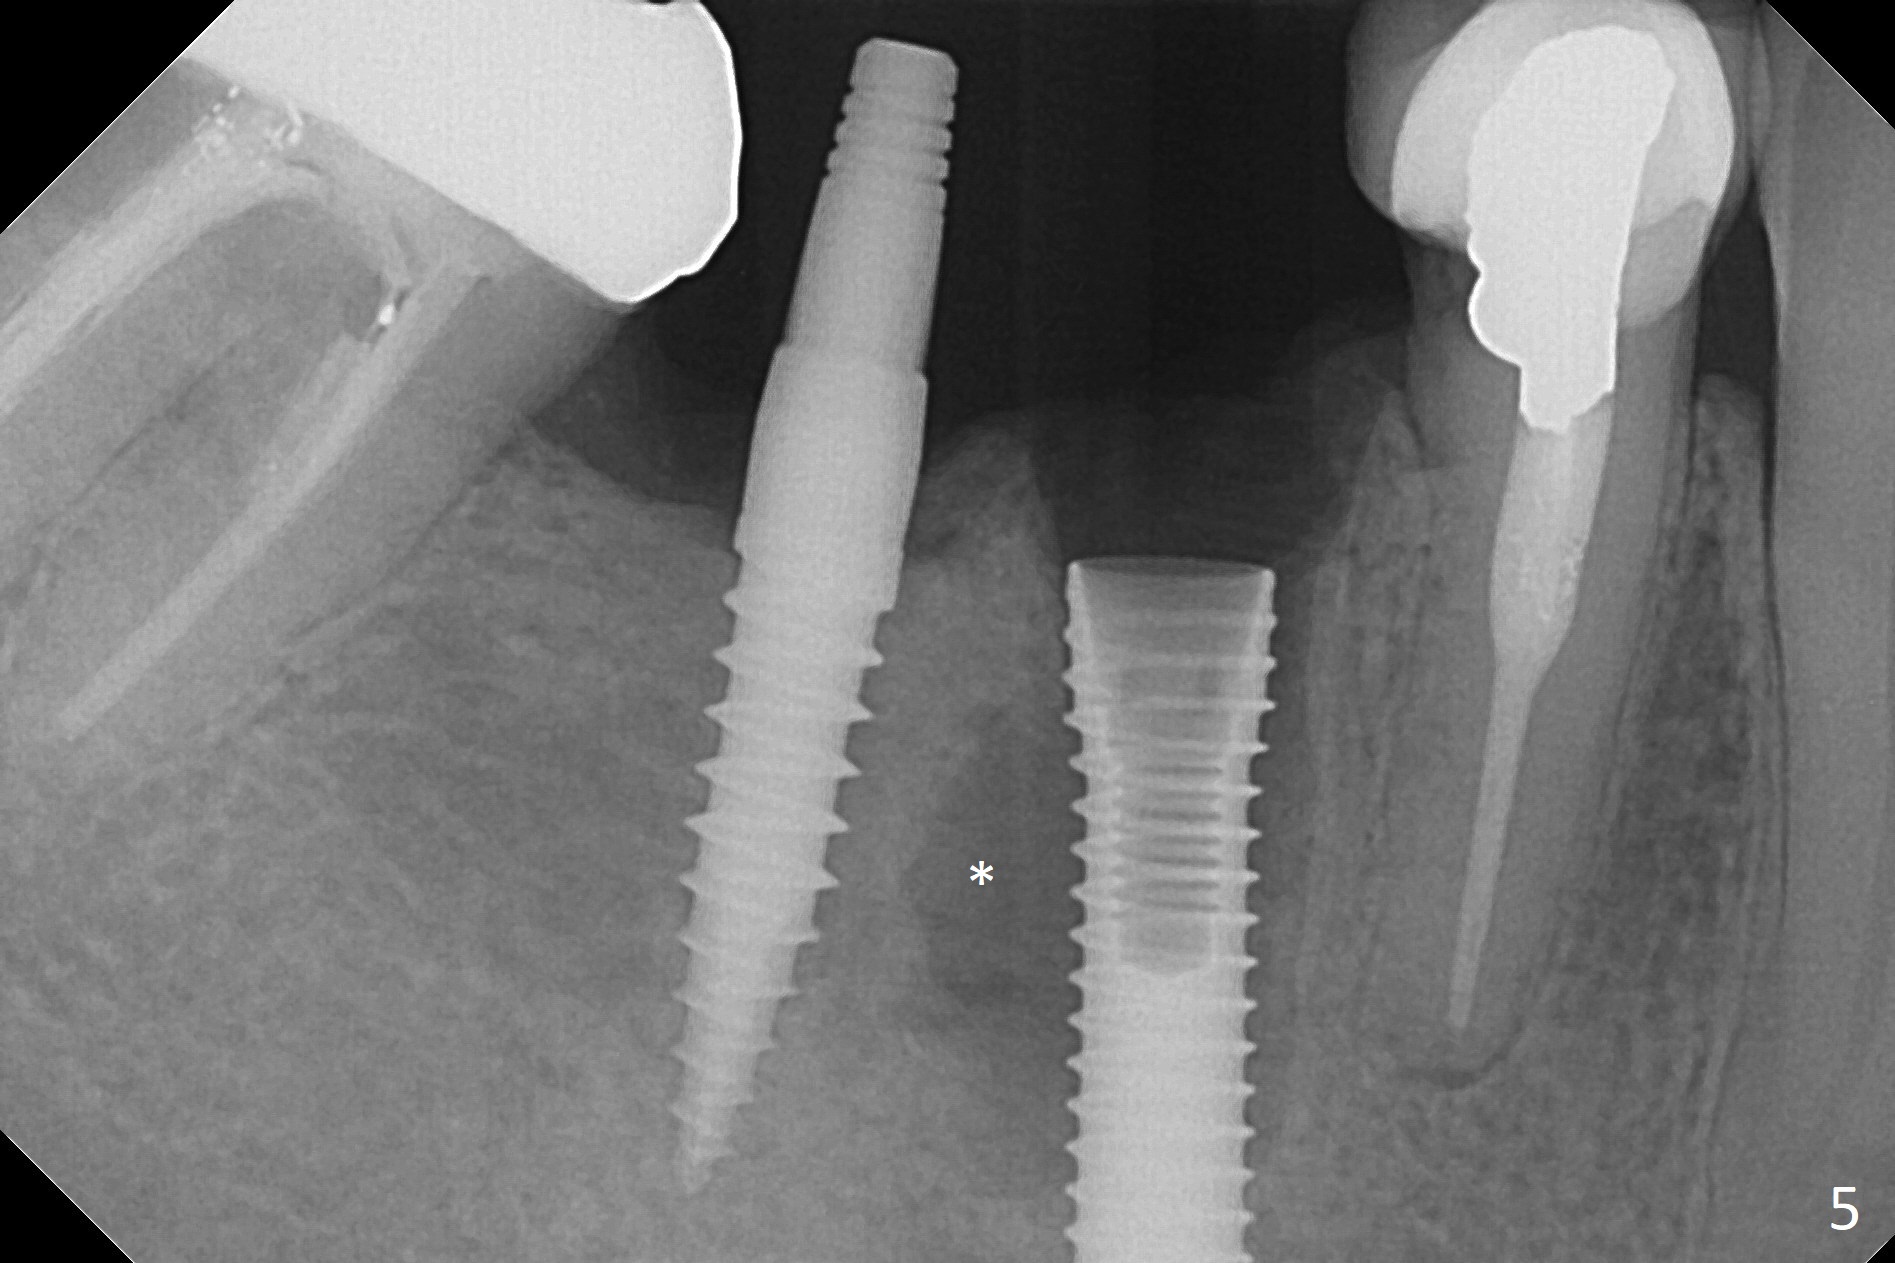

Preop examination shows that the buccal plate at #30 is atrophic (Fig.1 *). The mesiodistal width of the pontic is narrow as compared to the retainer at #31 (Fig.2). It appears that a narrow implant should be placed at #30 and should be able to sustain functional loading. After ridge reduction at #30 (Fig.3 ^) and extraction and debridement at #29, osteotomies at these sites are initiated with 1.2 mm and 2 mm drills, respectively. Probably due to low bone density, the osteotomy at #29 drops deep and close the Mental Loop (red dashed line). While the trajectory at #30 improves, the osteotomy at #29 remains close to the Mental Loop (Fig.4), asymptomatic with infiltration anesthesia. A 3x12(2) mm 1-piece implant is placed at #30 and 3.8x16 mm 2-piece implant at #29 (Fig.5,6 with insertion torque >50 and <50 Ncm, respectively). The large distal defect at #29 (Fig.3,5 *, most likely due to post-related perforation) is later filled with bone graft (data not shown). After placing an abutment at #29 and suturing, periodontal dressing is applied. Three months later, the meisal gap of #29 disappears while the distal one reduces (Fig.7 *). The abutment is changed to 4.5x4(4) mm one before reprep for impression. There is no bone loss 9 months post cementation (Fig.8) or 3 years 9 months post cementation (Fig.9). In fact the crown is lost at #31. At repeated request from the patient, a prefabricated post and crown will be fabricated for short term purpose while an implant is going to be placed at #19. The new crown at #31 has no occlusal contact (Fig.10), which may change over time.